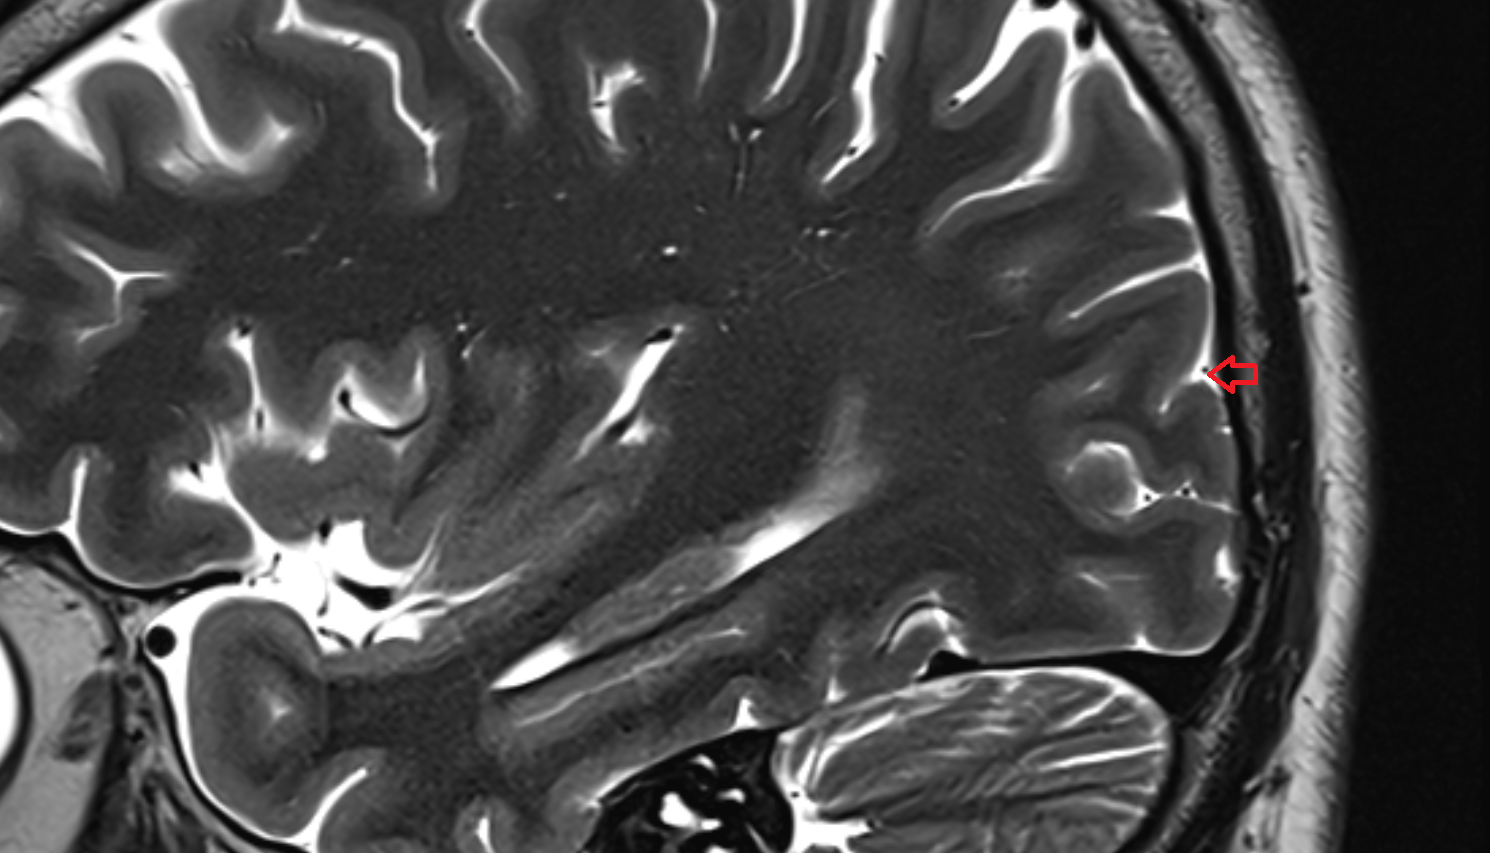

- Fetal brain

- Fetal caudate nucleus

- Fetal thalamus

- Fetal cerebellum

- Fetal occipital lobe

- Fetal temporal lobe

- Fetal parietal lobe

- Fetal frontal lobe

- Fetal third ventricle

- Fetal lateral ventricle